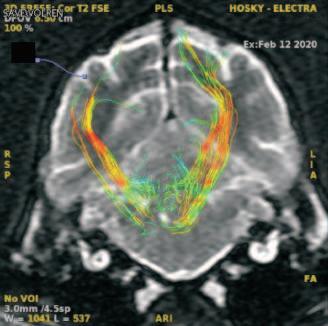

Tracto corticoespinal en vista coronal. (p. ??).

Uso del tensor de difusión como una herramienta de diagnóstico en las enfermedades del sistema nervioso central en perros. Reporte de un caso en un husky siberiano con alteraciones del comportamiento.

Use of the diffusion tensor as a diagnostic tool in diseases of the central nervous system in dogs. Report of a case in a Siberian husky with behavioral alterations. .